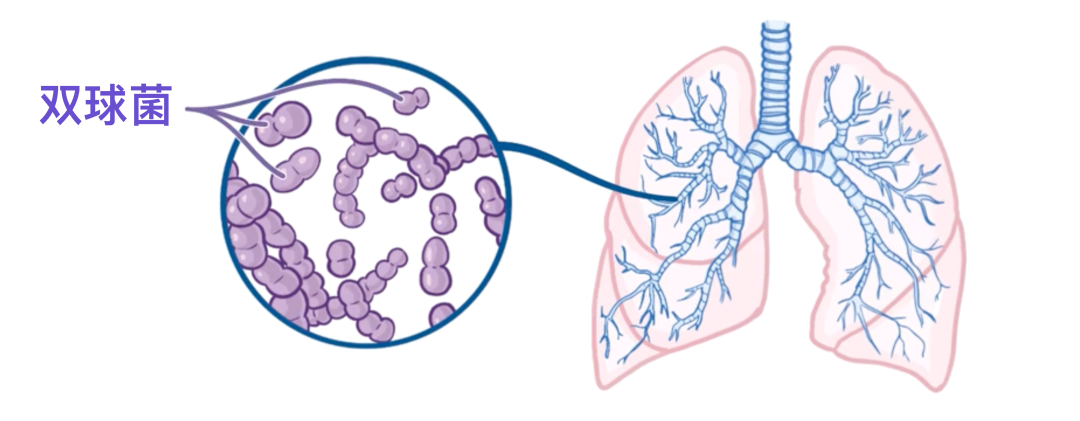

肺炎链球菌(Streptococcus pneumoniae,简称 Strep. pneumoniae)这个名字可以分解来理解:strepto- 意为“成链”,-coccus 意为“球形”,而pneumoniae则说明它能引起肺炎——这点不难理解。

因此,肺炎链球菌是呈圆形的细菌,常常成链状生长,通常以矛头状的成对形式出现,被称为双球菌。

它是社区获得性肺炎最常见的致病菌,也就是说,是在医院之外感染的肺炎的主要病因。